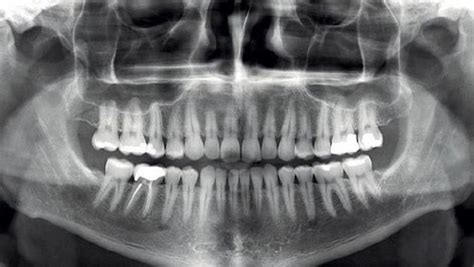

La ortopantomografía, también conocida como radiografía panorámica, es una prueba de diagnóstico por imagen que permite visualizar toda la boca en una sola toma. Es una herramienta fundamental en la odontología moderna. Gracias a ella, el equipo médico puede evaluar con precisión el estado de los dientes, huesos maxilares y articulaciones temporomandibulares.

Una ortopantomografía es una radiografía que muestra en una única imagen de formato panorámico la totalidad de las estructuras de la boca: maxilares, mandíbula y los dientes. También se observan en ella las articulaciones temporomandibulares y los senos maxilares.

A diferencia de las radiografías intraorales, que solo muestran pequeñas secciones de la dentadura, esta técnica abarca desde el maxilar superior hasta la mandíbula, incluyendo estructuras óseas, senos maxilares y articulaciones.